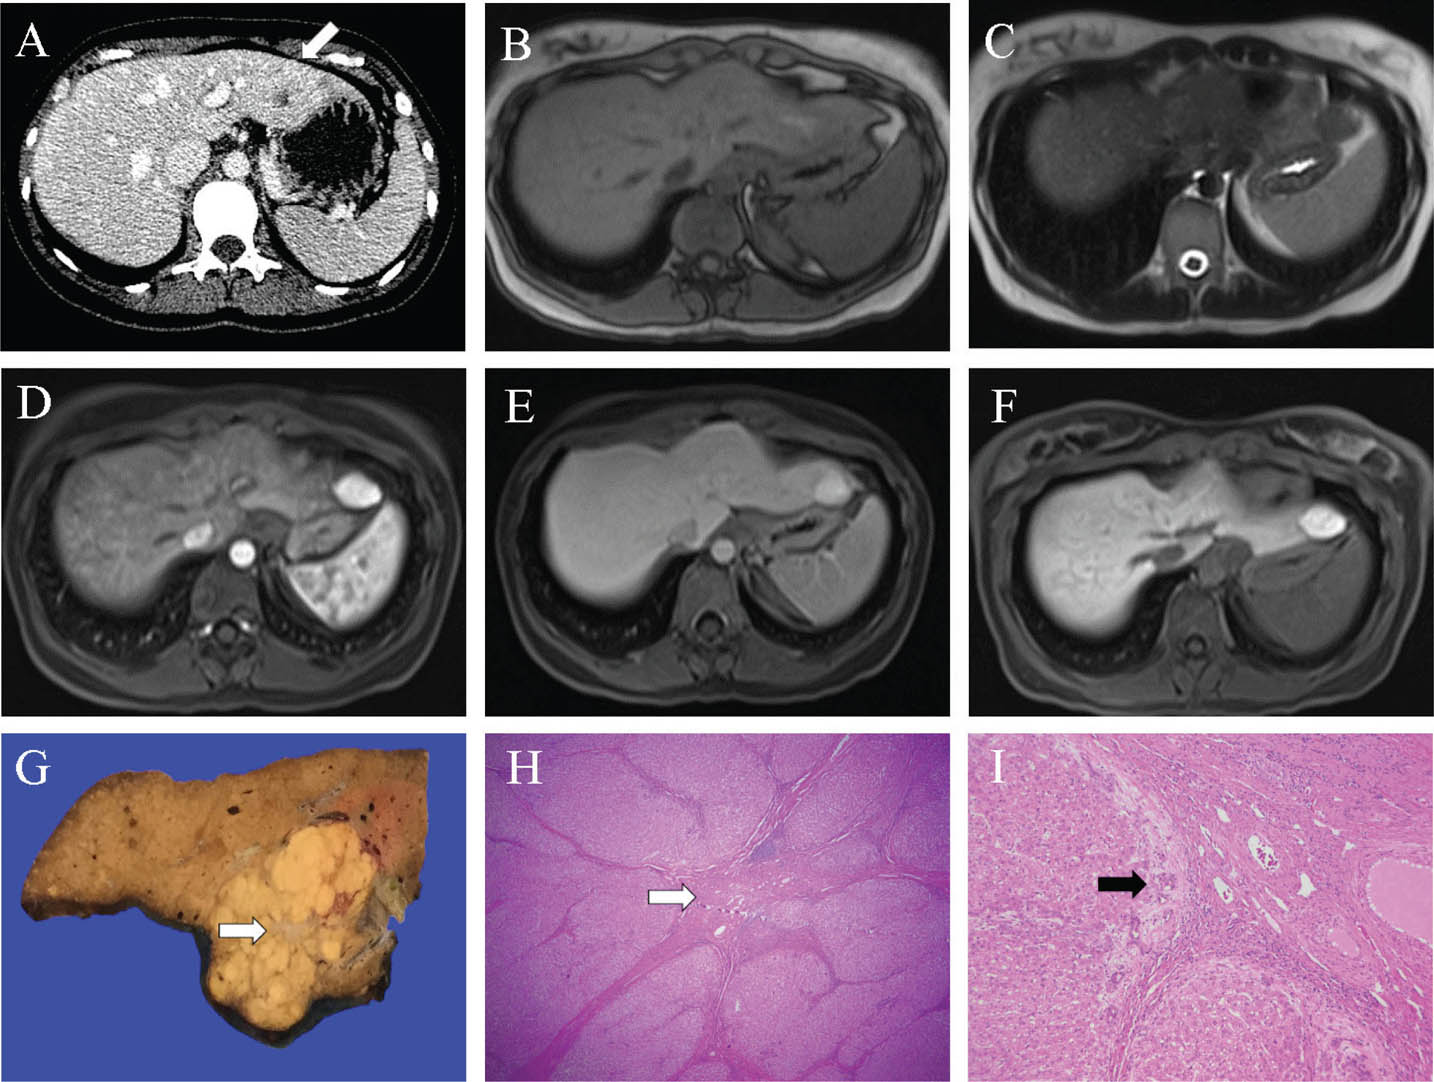

Fig 2

Figure 2. Representative images of hepatocellular adenoma. A and B. The large lesion (>5 cm) in segments 5 and 6 shows signal loss on the opposed phase T1 weighted image (B) compared to the in-phase T1 weighted image (A) denoting microscopic fat content. C. The lesion shows heterogeneous high signal on the T2 weighted image. D, E, and F. Following gadolinium administration, the lesion shows heterogeneous arterial (D) and portal phase (E) hyperenhancement and delayed phase washout (F). An ancillary finding of an enhancing capsule is depicted in (E) and (F). G. A partial hepatectomy from a separate patient shows a tan and poorly defined lesion grossly, with areas of hemorrhage and necrosis. H. Microscopically the neoplastic lesion (white arrow) shows an absence of portal tracts and is notably different from the background parenchyma (black arrow). I. Benign hepatocytes are arranged in cell plates up to two cells thick. Slides are stained with Hematoxylin and Eosin. Total image magnification: H - 25X; I - 400X.

Imaging features of HCA are often varied, with slightly different characteristics depending on the subtype. Hemorrhage with possible subsequent calcification, fat, and encapsulation may be seen. Of note, HCAs 5 cm or larger are at higher risk for both hemorrhage and malignant transformation into HCC, and require close imaging follow up. Males with HCAs are often treated by prophylactic surgical resection, particularly for solitary or large lesions, as a result of the increased incidence of the beta-catenin subtype.

Ultrasound is nonspecific, demonstrating a well-circumscribed lesion with variable echogenicity, more often hyperechoic. CEUS may increase specificity, particularly showing centripetal arterial flow, differentiating HCA from FNH, which typically illustrate a centrifugal arterial flow. Multiphasic contrast-enhanced CT demonstrates a well-circumscribed mass, which is typically isoattenuating on the unenhanced phase, with heterogeneous arterial phase hyperenhancement, usually returning to near isoattenuation on portal-venous phase and delayed phase imaging. Following hyperenhancement, contrast washout (hypoenhancement on the portal-venous and delayed phases) may be seen in both CT and MRI, mimicking malignant lesions.

On MRI, T1WI and T2WI signal intensities are variable, depending on the presence of fat, hemorrhage, and calcification. A high signal on fat-saturated T1WI denotes the presence of intratumoral hemorrhage. Contrast-enhanced phases are similar to CT, with early arterial enhancement, and are typically isointense on portal-venous phase imaging. HCAs are predominantly hypointense on hepatobiliary phase gadoxetic acid imaging, an important distinction from FNH. Opposed phase T1WI and fat-saturated T1WI are helpful to demonstrate microscopic fat and macroscopic fat, respectively, a characteristic feature of HNF1α-inactivated HCAs. Conversely, inflammatory HCAs have a characteristic high signal peripheral rim on T2WI, attributed to sinusoidal dilatation, termed the “atoll sign” (15).